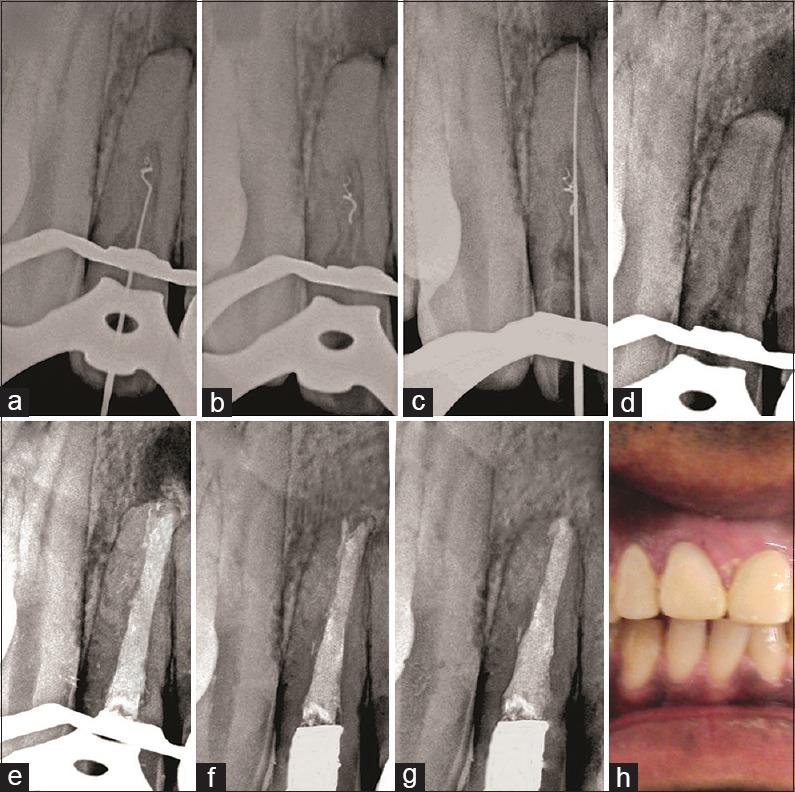

Treating pathological defects that are caused by resorption in teeth can be challenging. The task is complicated further if the resorption extends beyond the restrains of the root. The aim of this report is to describe a case of extensive internal tunneling resorption (ITR) associated with invasive cervical resorption (ICR) in a maxillary right lateral incisor and its nonsurgical treatment. A 22-year-old male was referred to the department of endodontics with a chief complaint of discolored maxillary right lateral incisor or tooth 12 and a history of trauma. An extensive ITR associated with ICR accompanied by apical periodontitis was detected on a preoperative radiograph which was confirmed on a cone-beam computed tomography (CBCT) scan in a maxillary lateral incisor. After chemomechanical debridement and withdrawal of a separated file in the canal, calcium hydroxide was placed as an intracanal medicament for 2 weeks. Biodentine (BD) was used to obturate the defect as well as entire root canal system and to restore ICR. On a 5-year follow-up, the tooth was functional, and periapical healing was evident. Based on results of this case, successful repair of ITR associated with ICR with BD may lead to resolution of apical periodontitis. Trauma to teeth may lead to resorption which may be internal, external, and or a combination of both which may be asymptomatic in some patients. Preoperative assessment using CBCT imaging achieves visualization of location and extents of resorptive defects. Bioactive materials like BD may lead to favorable results in treating such extensive defects.

治疗由牙齿吸收引起的病理缺陷可能具有挑战性。如果吸收超出牙根范围,任务会更加复杂。本报告的目的是描述一例上颌右侧侧切牙广泛的内部隧道状吸收(ITR)合并侵袭性颈部吸收(ICR)及其非手术治疗的病例。一名22岁男性因上颌右侧侧切牙(即12号牙)变色及有外伤史被转诊至牙髓病科。术前X线片显示上颌侧切牙存在广泛的ITR合并ICR,并伴有根尖周炎,锥形束计算机断层扫描(CBCT)证实了这一情况。在进行化学机械清创并取出根管内分离的锉后,放置氢氧化钙作为根管内药物2周。使用生物活性牙本质(BD)封闭缺损以及整个根管系统,并修复ICR。在5年的随访中,该牙功能正常,根尖愈合明显。基于该病例的结果,用BD成功修复合并ICR的ITR可能会使根尖周炎得到缓解。牙齿外伤可能导致吸收,吸收可能是内部的、外部的或两者皆有,在某些患者中可能无症状。使用CBCT成像进行术前评估可实现对吸收性缺损的位置和范围的可视化。像BD这样的生物活性材料在治疗此类广泛缺损时可能会产生良好效果。